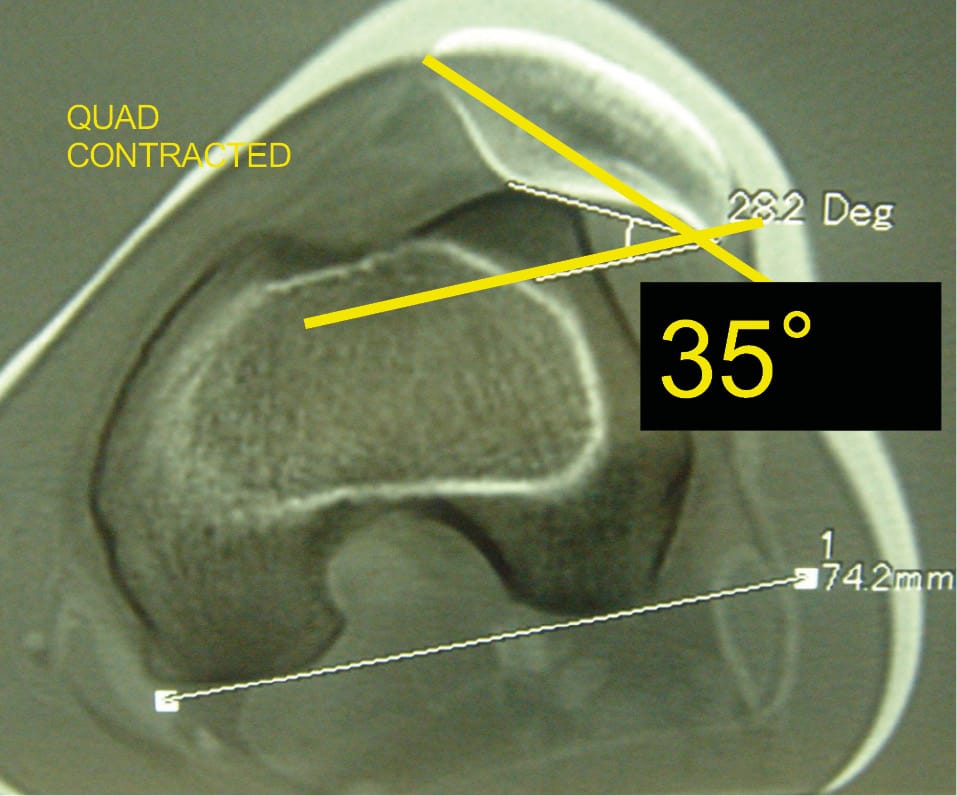

The third factor retained in 1987 was patellar tilt.

Patellar tilt is the expression of malalignment of the patella in the horizontal plane. Patellar tilt depends on bone anatomy but also on the retinacula or patellar ligaments and the quadriceps muscle.

The presence of patellar tilt greater than 20° with relaxed quadriceps was found in 83% of patients belonging to the objective patellar instability group. This tilt was initially attributed to VMO dysplasia. Our subsequent work showed that trochlear dysplasia, patellar height, and the TT-TG value evidently influenced patellar tilt.

The patellar tilt is 35° with contracted quadriceps. When the patella is high, it is sometimes necessary to superimpose the trochlear and patellar sections (Figure 31).